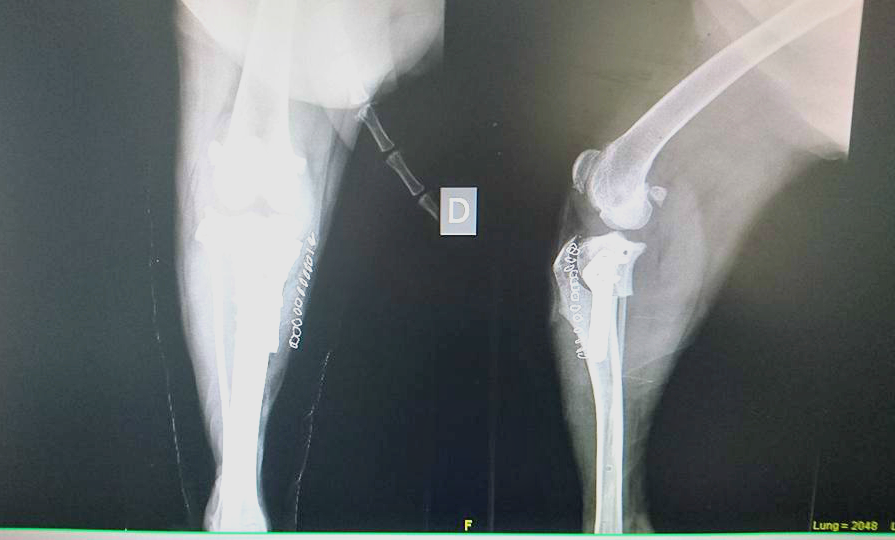

CALVATONE – Una nuova vita per lui. La seconda, in attesa di una terza che sarà al termine del tunnel in cui Capo, meticcio arrivato a ‘La cuccia e il nido’ di Calvatone, è precipitato. Una storia, la sua, come tante. Quella di chi prende un cane e poi – di fronte alle difficoltà di una convivenza – ci rinuncia. “Capo – raccontano i volontari del canile di Calvatone – è cresciuto in famiglia, e sarebbe dovuto essere così per sempre, ma qualcosa è andato storto e poche settimane fa ha fatto il suo ingresso da noi, al Canile Rifugio la Cuccia e il Nido Anpana Onlus di Calvatone. Capo è stato rinunciato dalla famiglia per presunta aggressività nei confronti della figlia. Nessun educatore, nessuno si è rimboccato le maniche, per lui c’era solo un box ad attenderlo. Capo dopo i primi giorni di disorientamento, durante i quali si disperava e tremava tutto il tempo per la paura, si è rivelato il contrario di quello che gli ex padroni avevano riferito: è un bravissimo cane dagli occhi dolci e speranzosi, con la coda perennemente in movimento per ricevere una coccola, è buono e docile con tutti i volontari e gli operatori che fin da subito l’hanno curato e amato”. Le ‘disgrazie’ però non vengono mai sole. I volontari notano in capo una difficoltà di movimento e decidono di accertarsi delle reali condizioni del meticcio ‘sorridente’. “Una persistente zoppia alle zampe posteriori, per cui sono stati effettuati alcuni accertamenti. Speravamo non fosse qualcosa di grave ma purtroppo non è stato così. Le lastre hanno evidenziato la rottura completa del crociato della zampa posteriore destra, ed il lesionamento del crociato posteriore sinistro”. Un problema, benché piuttosto serio, risolvibile. Capo va sotto ai ferri grazie alla disponibilità di Anpana a farlo curare e a quella della Clinica Sant’Eusebio di Asola disposta a venire incontro al canile con le spese – ingenti – di quel tipo di operazione. “Il 10 marzo Capo ha subito l’operazione a carico del crociato posteriore destro presso la Clinica Sant’Eusebio di Asola, e subirà un ulteriore intervento al crociato sinistro nei prossimi mesi. La prima operazione (Osteotomia piatto tibiale con lama 22,5 mm, rotazione piatto tibiale, fissazione con placca TPLO 3,5 mm 6 fori, sutura cute e sottocute e bendaggio di Robert Jones, ndr) è andata a buon fine, ora Capo dovrà restare a riposo”. Operazione, lastre e controlli sono costati 900 euro. Tutti sostenuti da Anpana. “Non potevamo non intervenire – spiega Patrizia Storti di Anpana – e così abbiamo deciso di procedere. La clinica ci ha fatto un prezzo di favore, lo staff è stato molto disponibile e di questo li ringraziamo enormemente. A favore di Capo e delle sue cure si è deciso di creare una raccolta fondi. Come ben sapete le spese qua in canile sono davvero tante, le rinunce di proprietà e gli abbandoni continuano e i cani che arrivano hanno spesso bisogno di analisi e cure mediche costose”. Per Capo – il meticcio sorridente – si è aperta una raccolta. Diverse le strade che possono consentire un aiuto al meticcio: l’adozione a distanza, il versamento di una donazione sul c/c presso la Banca CARIPARMA di San Giovanni in Croce, IBAN: IT 25 N 06230 57130 000043318875 – Causale: Donazione pro Capo, una donazione PayPal cliccando sul pulsante “fai una donazione” sulla nostra pagina facebook (questo metodo è totalmente sicuro ed affidabile, nonché facile e veloce, accetta tutte le carte di credito, anche PayPal si può utilizzare anche dall’estero), l’iniziativa “Un Uovo per Fido” con cui si possono sostenere le cure di Capo attraverso le uova solidali al cioccolato al latte o fondente che si possono trovare presso l’Ufficio del Canile Rifugio tutti i giorni dalle 14 alle 18, weekend compreso. Capo avrà una seconda possibilità in questa sua seconda vita. In attesa di una terza, magari al caldo di una casa con una famiglia dal cuore grande, disposta a prendersene cura.